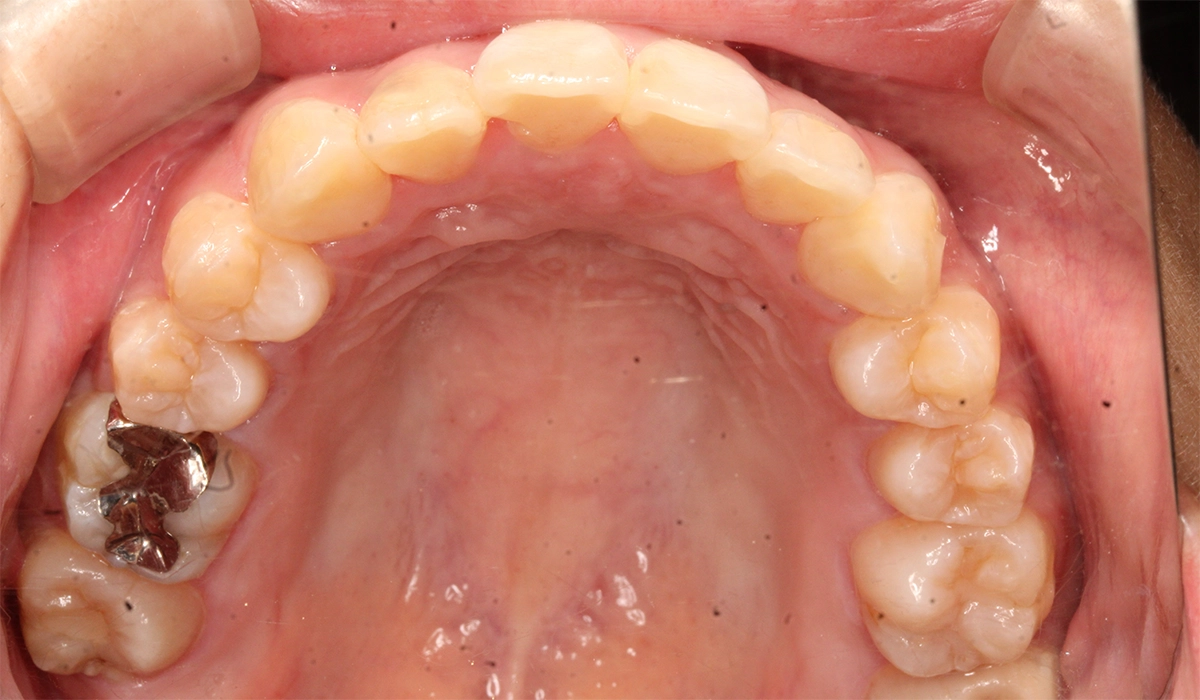

術前:上顎

術後:上顎